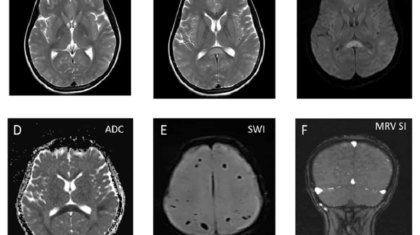

28 years old female presented on 5th post partum day with altered sensorium and one episode of seizures. No history of elevated blood pressure. Sodium level at time of